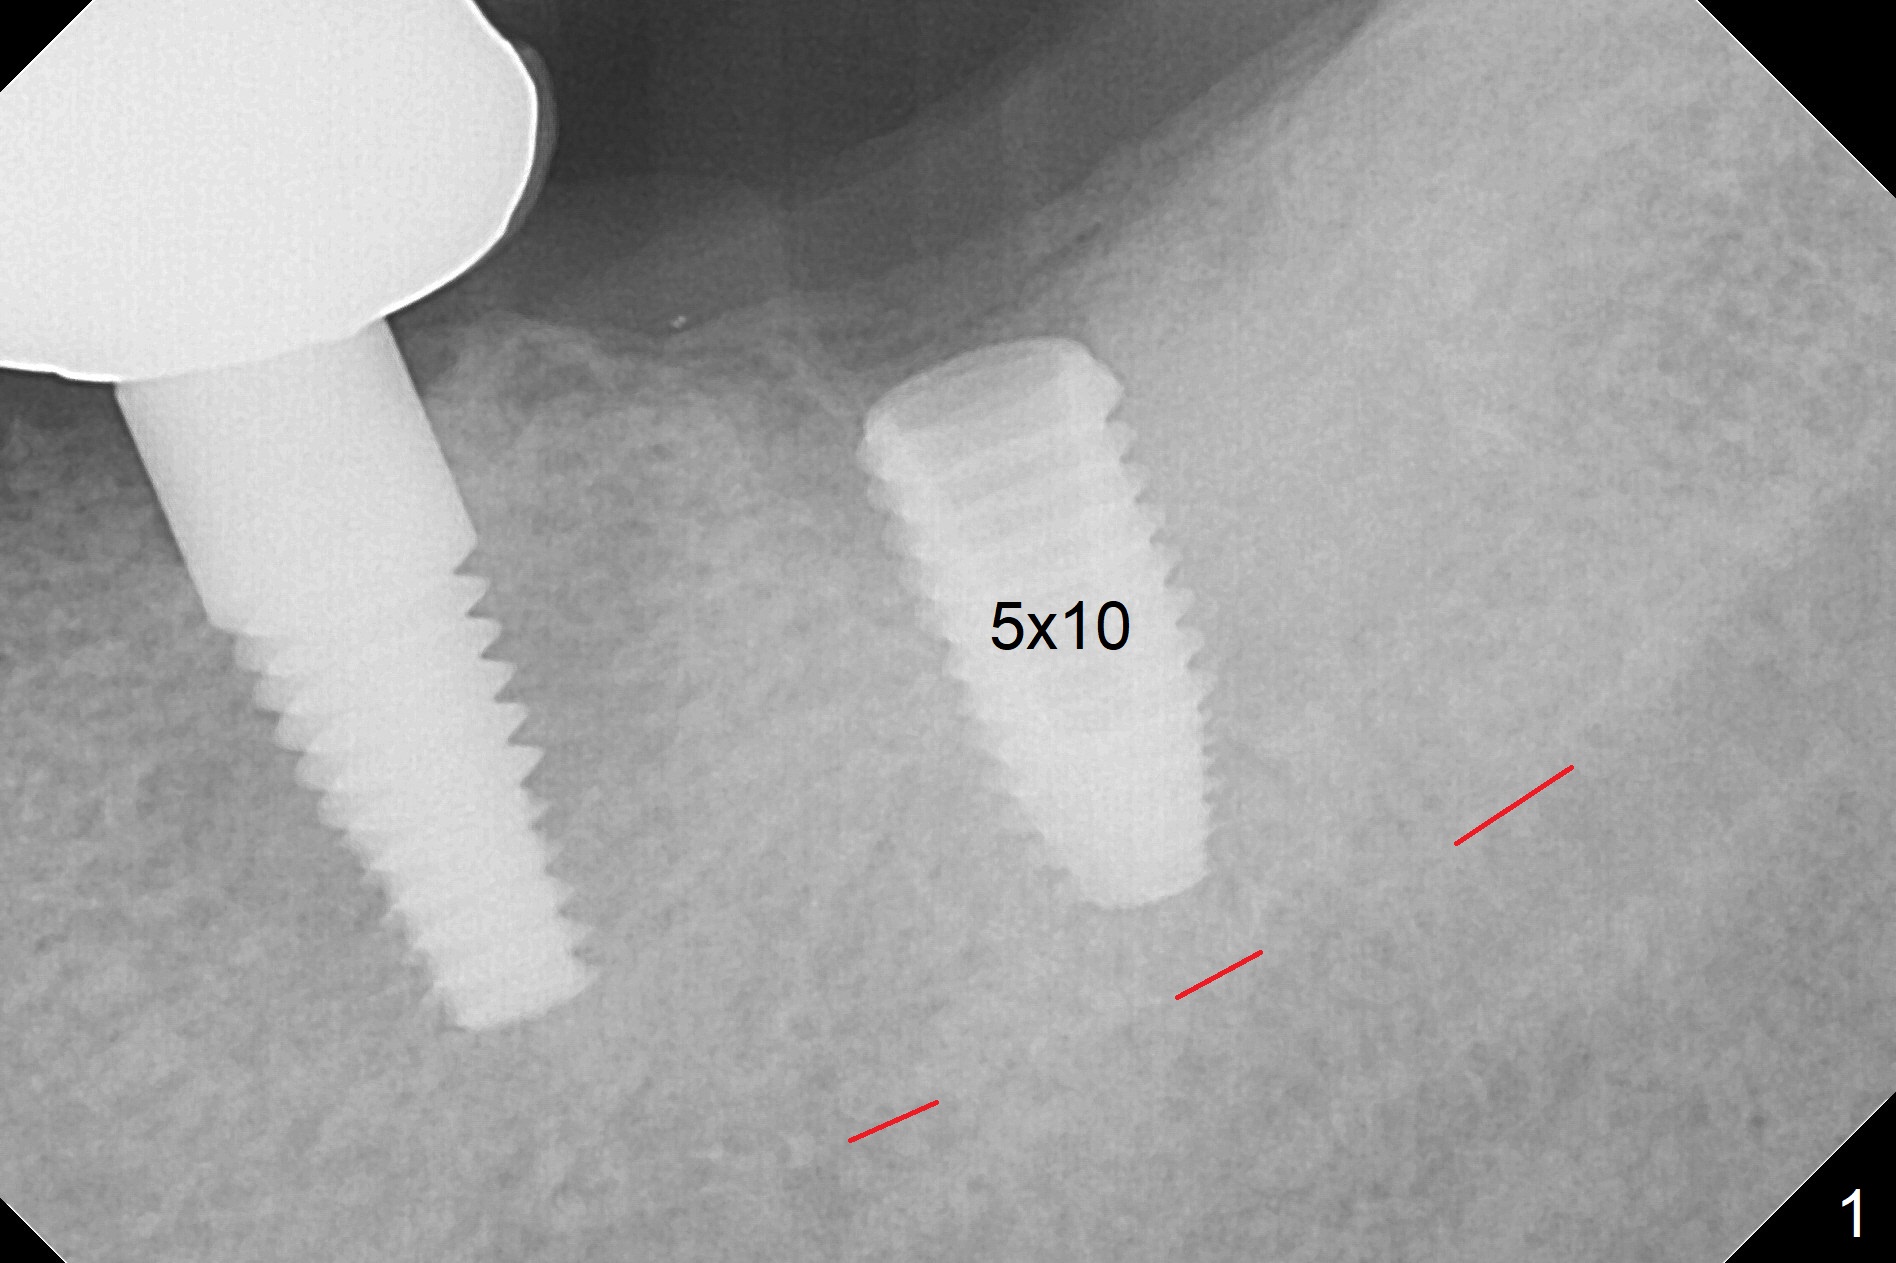

Depth Control of Guide for 2nd Molar

When the surgical guide is pressed hard at the 1st molar area, the guide appears to sink down ~ 1 mm.  The last drill and a 5x10 mm implant are placed as the guide is being pressed hard (Fig.1).  The implant appears placed deeper than the design.